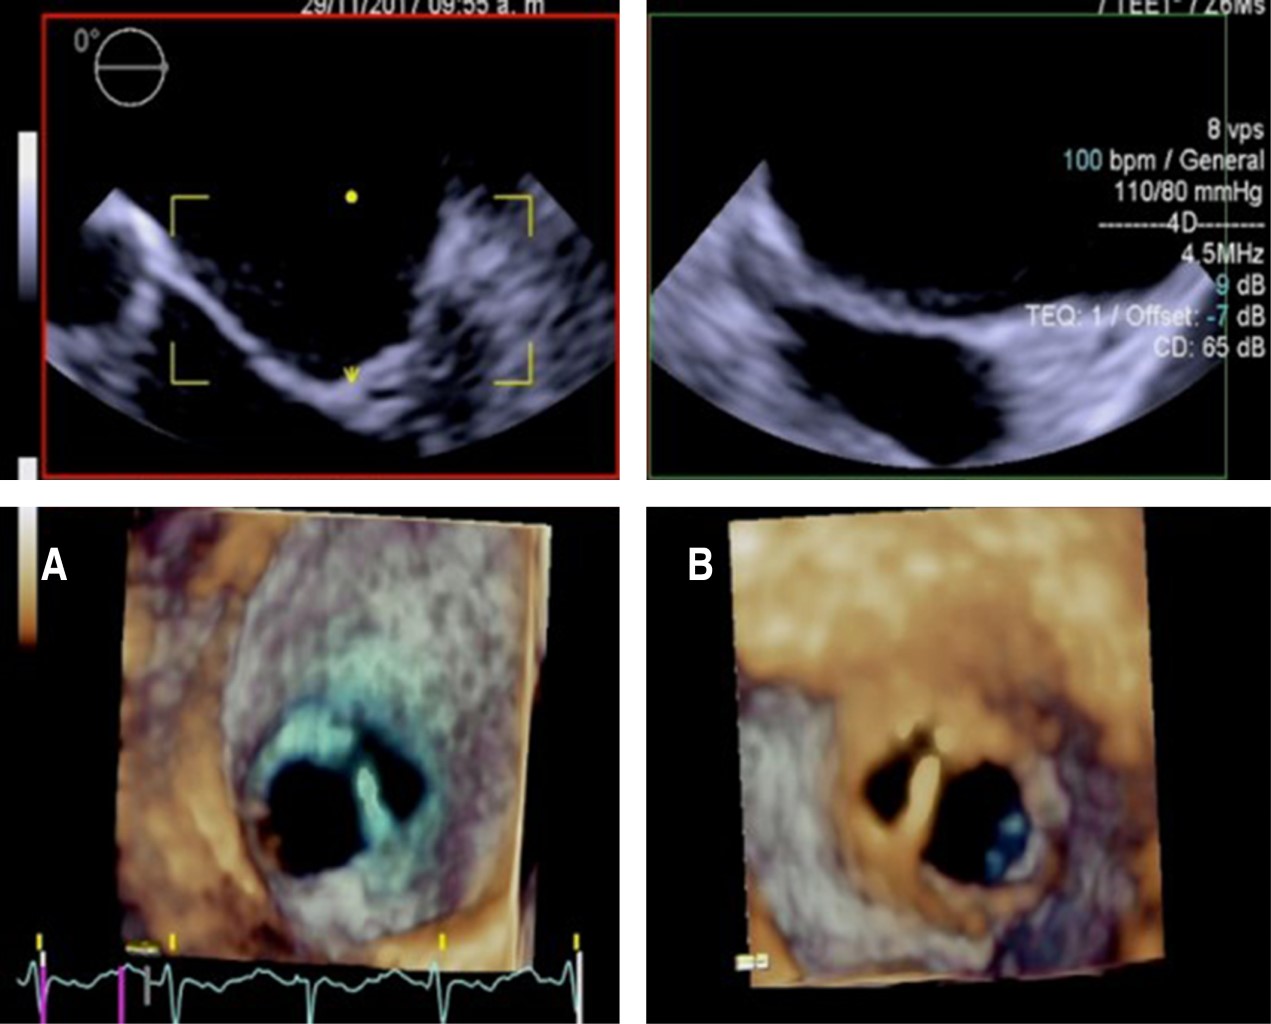

Doble orificio de válvula mitral en mujer asintomática joven con coartación aórtica y válvula aórtica bicúspide

Guevara-Canceco APG, Aceves-Millán R, Zaldivar-Fujigaki JL, Sandoval-Castillo LD, Ixcamparij-Rosales CH, Morales-Portano JD

Las cardiopatías congénitas en México ocupan el segundo lugar de malformaciones congénitas en los recién nacidos, con una incidencia de 0.8-1.4%. El doble orificio de la válvula mitral (DOVM) es una cardiopatía congénita rara, con una incidencia reportada de 0.05%. Esta malformación consiste en la presentación anatómica de dos orificios mitrales comúnmente asociada a otras malformaciones congénitas como defectos septales, malformaciones completas o parciales del canal atrioventricular, coartación aórtica, tetralogía de Fallot, comunicación interauricular o interventricular, anomalía de Ebstein y persistencia del conducto arterioso. Las características clínicas son variables e incluso pueden pasar desapercibidas y ser diagnosticadas hasta la edad adulta. Se presenta el caso de una mujer joven el cual se encuentra asintomática con diagnóstico de hipertensión arterial, que durante una revisión de rutina fue diagnosticada con múltiples cardiopatías congénitas, de las cuales, su relación está poco descrita en la literatura, siendo este el tercer caso reportado. En la actualidad las técnicas de imagen multimodal permiten la mayor caracterización de las lesiones tanto de la valva como del aparato valvular, con la intención de realizar un abordaje diagnóstico y terapéutico integral para ofrecer el mayor beneficio al paciente.

Figura 1

Figura 2

Figura 3

Figura 4

Figura 5